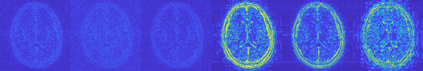

Magnetic Resonance Imaging (MRI) has excellent soft tissue contrast but is hindered by an inherently slow data acquisition process. Compressed sensing, which reconstructs sparse signals from incoherently sampled data, has been widely applied to accelerate MRI acquisitions. Compressed sensing MRI requires one or more model parameters to be tuned, which is usually done by hand, giving sub-optimal tuning in general. To address this issue, we build on previous work by the authors on the single-coil Variable Density Approximate Message Passing (VDAMP) algorithm, extending the framework to multiple receiver coils to propose the Parallel VDAMP (P-VDAMP) algorithm. For Bernoulli random variable density sampling, P-VDAMP obeys a "state evolution", where the intermediate per-iteration image estimate is distributed according to the ground truth corrupted by a zero-mean Gaussian vector with approximately known covariance. To our knowledge, P-VDAMP is the first algorithm for multi-coil MRI data that obeys a state evolution with accurately tracked parameters. We leverage state evolution to automatically tune sparse parameters on-the-fly with Stein's Unbiased Risk Estimate (SURE). P-VDAMP is evaluated on brain, knee and angiogram datasets and compared with four variants of the Fast Iterative Shrinkage-Thresholding algorithm (FISTA), including two tuning-free variants from the literature. The proposed method is found to have a similar reconstruction quality and time to convergence as FISTA with an optimally tuned sparse weighting and offers substantial robustness and reconstruction quality improvements over competing tuning-free methods.